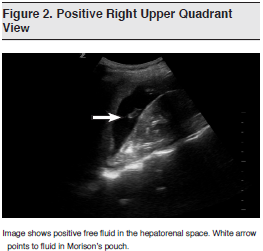

As early as 1971, the utility of ultrasound scanning for patients with splenic injuries was documented.2 It was not until the early 1990s, however, that ultrasound became widely advocated and studied in patients with blunt abdominal trauma.3-6 Since then, ultrasound has been included in the Advanced Trauma Life Support protocol of the American College of Surgeons6 and in the Eastern Association for the Surgery of Trauma (EAST) guidelines for the management of blunt abdominal trauma.8 The American College of Radiology also recommends the use of ultrasonography — and specifically, the FAST scan — to evaluate for free or localized intra-abdominal fluid collections.9 (See Figures 1 and 2)

The traditional FAST examination involves 4-quadrant scanning with views of the hepatorenal space, the perisplenic and splenorenal interface, the pelvis, and the pericardium through a subxiphoid or parasternal approach. Recently, authors have studied an extended version of the FAST examination, referred to as the Extended Focused Assessment with Sonography for Trauma (E-FAST). In addition to the 4-quadrant views of the FAST, the E-FAST includes views of both hemithoraces at the levels of the diaphragm-abdominal interface and over bilateral anterior chest walls. (See Figure 3) It is designed to assess for pneumothorax in the anterior views and for pleural effusion or hemothorax in the supradiaphragmatic views.